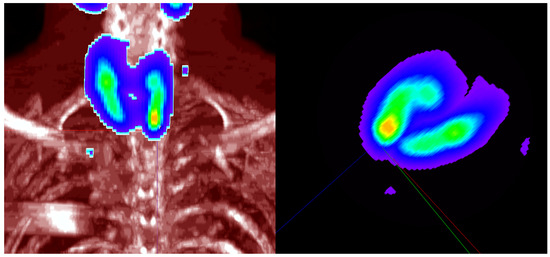

Two types of data were considered: real volume and synthetic volume used in Monte Carlo test. Exemplary real volume was tested in this paper for illustrative purposes (Figure 1).

Figure 1.

Fusion coronal image of Single-Photon Emission Computed Tomography combined with Computed Tomography (SPECT/CT)—a lesion with slightly increased uptake in a lower left pole of thyroid gland corresponds with abnormal parathyroid gland (left). 3D view of parathyroid glands (right, SPECT only).

Proper 3D view with enhanced contrast and color allows visual inspection of parathyroid glands and some details of the structures are visible, including local maxima [27]. Maximal Intensity Projection (MIP) is used for the visualization of SPECT [45,46,47]. This solution indicates details such as local maxima of SPECT that are not visible for Average or Composite Intensity Projections [47] and removes artifacts from distant regions not related to parathyroid glands by the application of spherical region of interest [27]. Additional threshold for removal voxels with values below specified value improves visibility of region with parathyroid glands (Figure 1 right) [27]. This volume has complex structure and shows the importance of multiparameter mixtures for analysis.